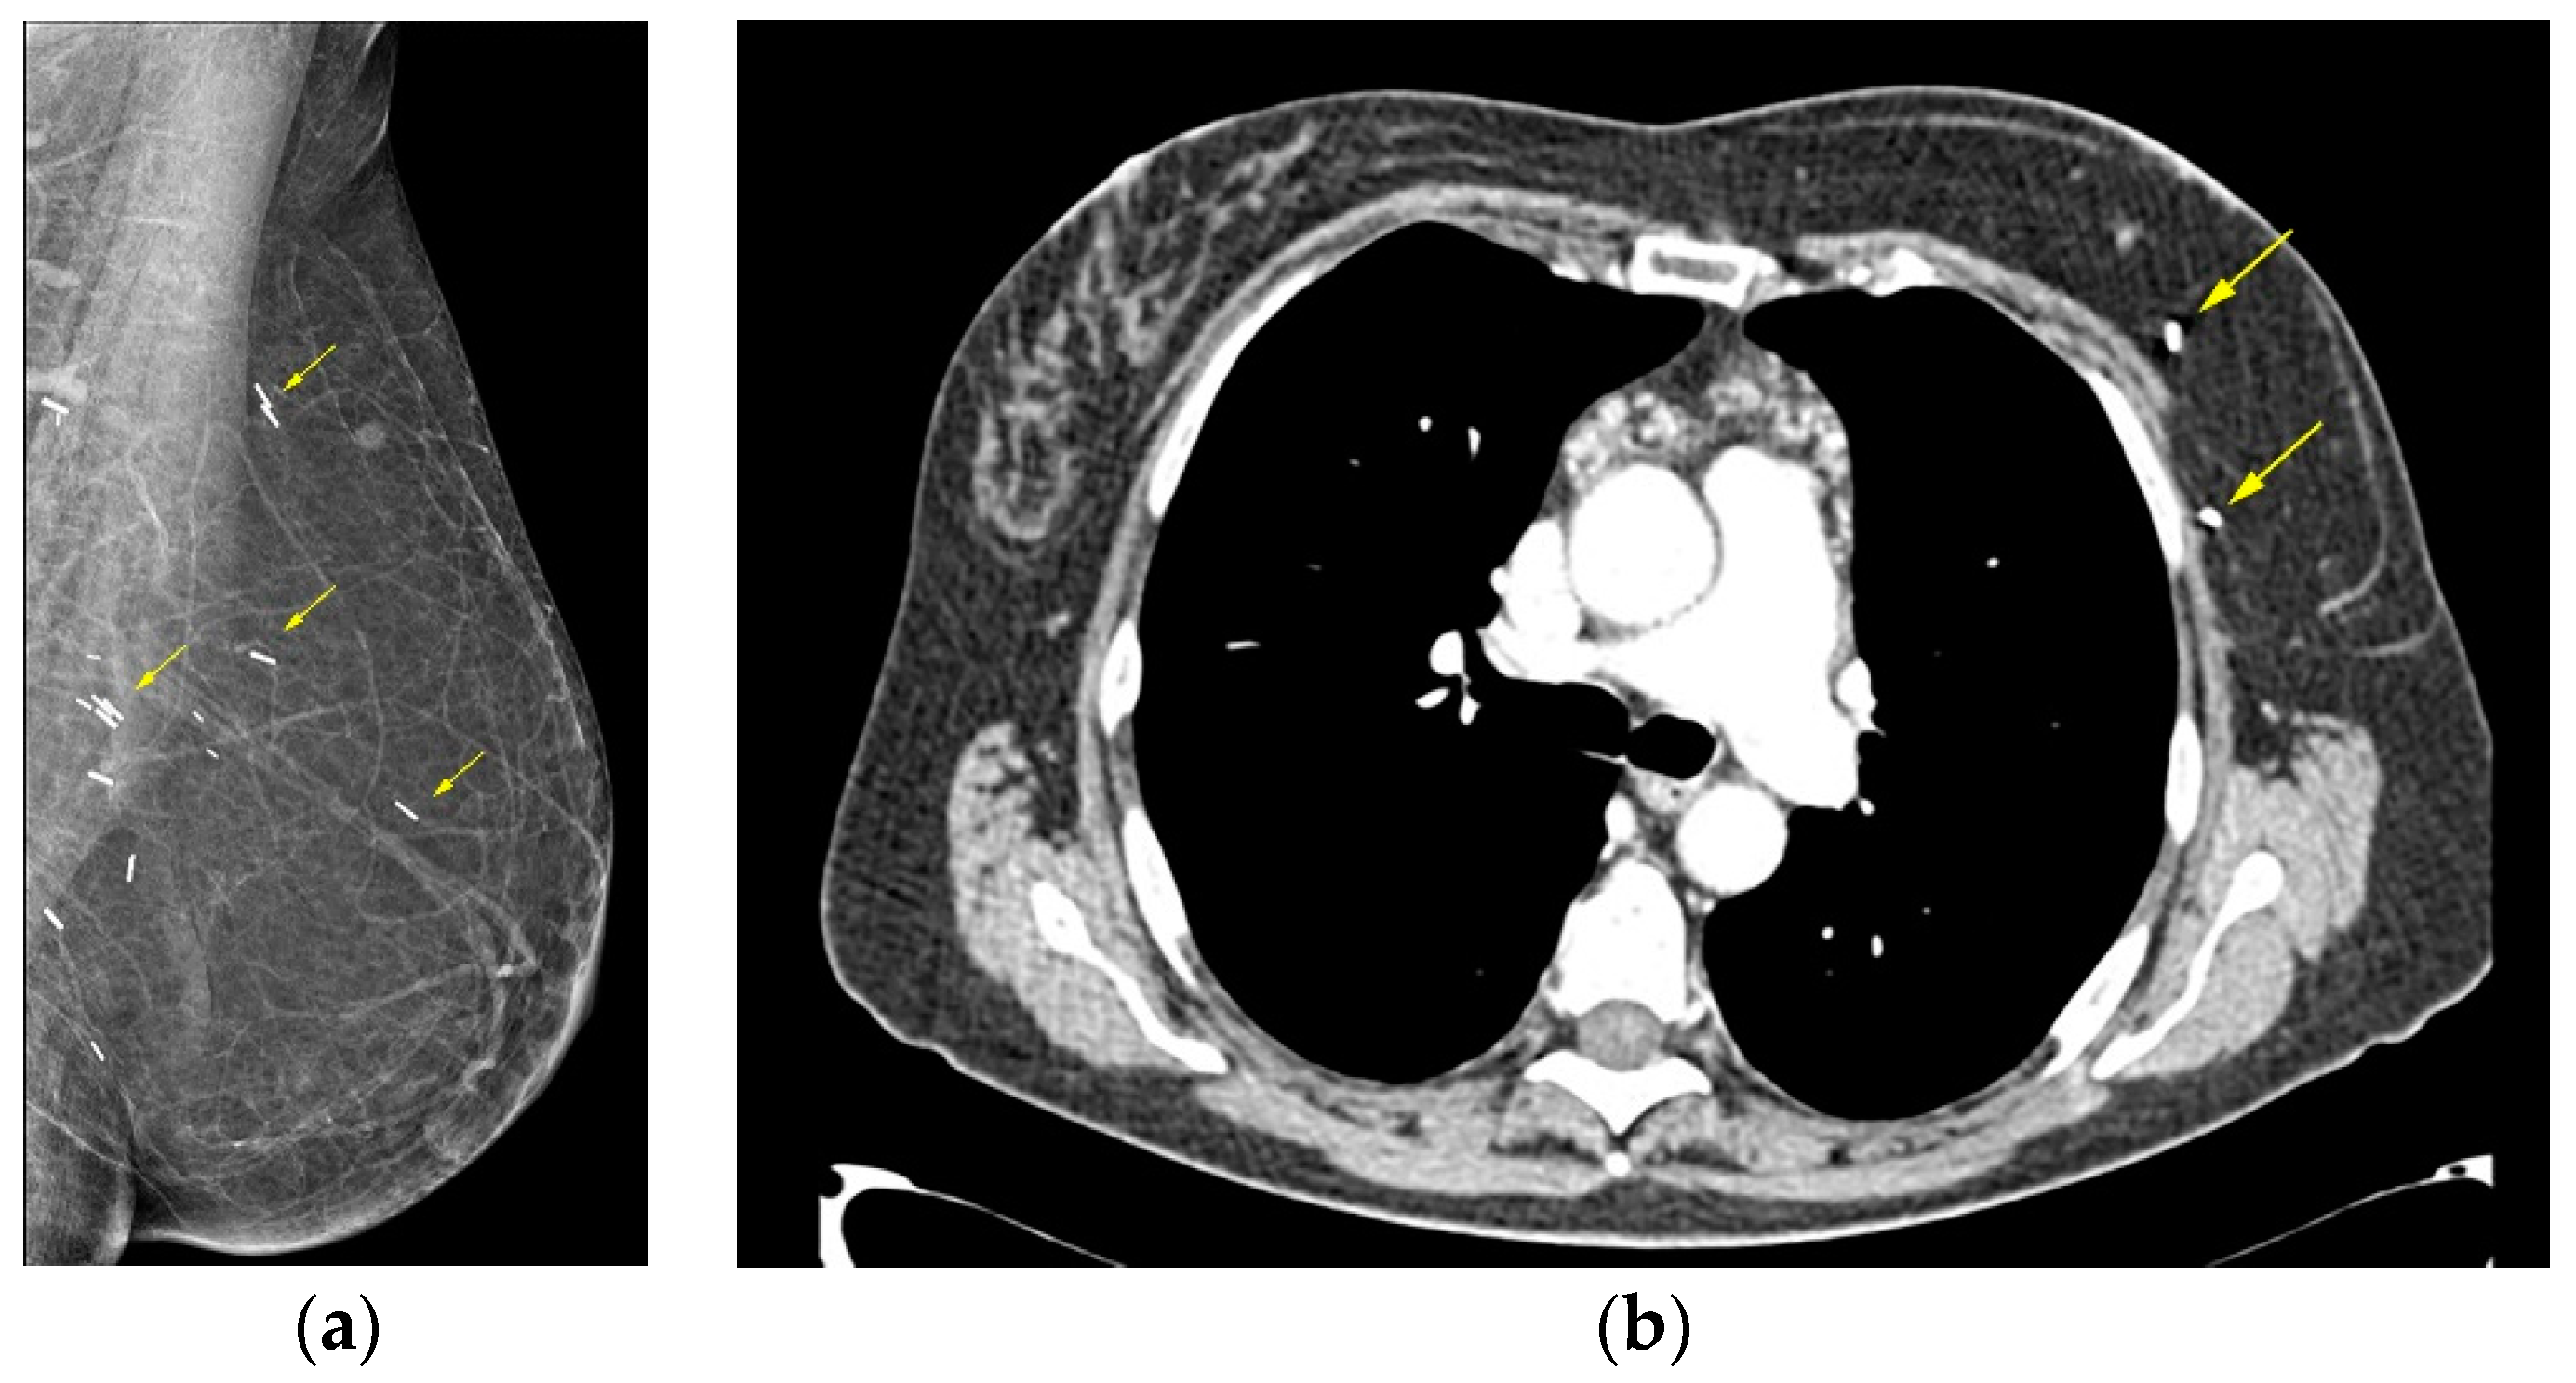

On mammography the reconstructed breast is consisted predominantly by fat and in case of muscle baring flaps muscle strands can be visible. Postoperative scarring and clips are common findings (Figure 1) [44].

Figure 1. Deep Inferior Epigastric Perforator (DIEP) reconstruction. (a) Mediolateral Oblique mammographic (MLO) view of the reconstructed breast depicts essentially fatty tissue and surgical clips (arrows); (b) Axial thoracic CT scan confirms the presence of a viable DIEP reconstruction with no complications.